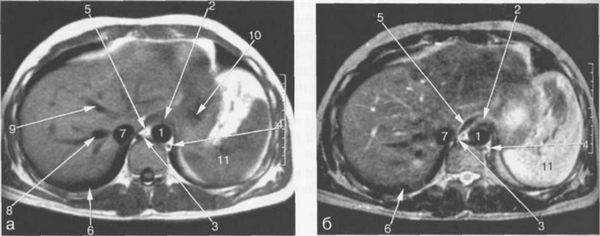

Рис. 11.9. МРТ брюшной полости в аксиальной плоскости на уровне печеночных вен.

1 — аорта; 2 — пищевод; 3 — непарная вена; 4 — полунепарная вена; 5 — спинной мозг; 6 — нижняя доля правого легкого; 7 — нижняя полая вена; 8 — правая печеночная вена; 9 — средняя печеночная вена; 10 — левая печеночная вена; 11 — левый желудочек сердца; 12 — ветви правой воротной вены; 13 — селезенка.

Рис. 11.10. МРТ брюшной полости в аксиальной плоскости на уровне пищеводно-желудочного перехода.

1 — аорта; 2 — пищеводно-желудочный переход; 3 — непарная вена; 4 — полунепарная вена; 5 — ножка диафрагмы; 6 — нижняя доля правого легкого; 7 — нижняя полая вена; 8 — правая печеночная вена; 9 -средняя печеночная вена; 10 — желудок; 11 — селезенка.

Рис. 11.11. МРТ брюшной полости в аксиальной плоскости на уровне печеночных вен.

1 — аорта; 2 — желудок; 3 — хвостатая доля печени; 4 — левая ветвь воротной вены; 5 — передние сегменты правой доли печени; 6 — задние сегменты правой доли печени; 7 — нижняя полая вена; 8 — правая печеночная вена; 9 — правая ветвь воротной вены; 10 — левая доля печени; 11 — селезенка; 12 — диафрагма.

Правая печеночная вена расположена в правой межсегментарной борозде, которая отделяет друг от друга передние и задние сегменты правой доли печени (рис. 11.12, 11.13). Левая печеночная вена располагается в левой межсегментарной борозде и разделяет внутренний и наружный сегменты левой доли печени (см. рис. 11.9). Серповидная связка также может использоваться в качестве ориентира, разделяющего внутренний и наружный сегменты левой доли печени.